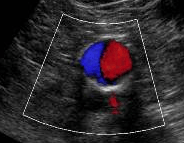

Ultrasound is done to detect aneurysms early, allowing for monitoring and treatment before they rupture. It is a painless, non-invasive test that locates the aneurysm, measures the dimensions and evaluates for plaque build up on the wall which may cause a narrowing.

Ultrasound is an effective and safe tool for the detection of aortic aneurysms and a highly accurate way to measure the size of an aneurysm with experience. Some aneurysms may pose difficulty in viewing due to their location, tortuosity features or calcific plaques limiting penetration of the soundwaves. We have many years of experience navigating these complications to provide your health care provider with accurate measurements and information. We provide your Doctor with extensive anatomical features and if the aneurysm is at a surgical size, further measurements to plan for your best treatment options.